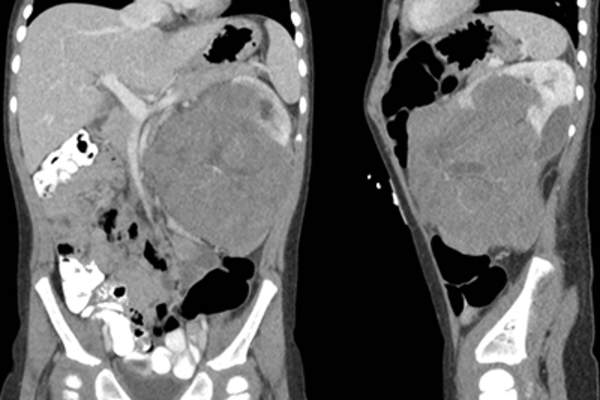

肾母细胞瘤分期

一旦肾母细胞瘤被诊断出来,下一步医生就要确定肿瘤处于什么阶段。有肾母细胞瘤五期它描述了癌症的程度和进展的程度。例如,第一阶段意味着癌症被控制在肾脏,并通过手术完全切除。第5阶段意味着两个肾脏在诊断时都有肿瘤:请在下一张幻灯片中阅读更多内容。

5期肾母细胞瘤

第5阶段显示两个肾脏都有肿瘤,这可能意味着两个肾脏都有异常组织发展成肿瘤。肿瘤不太可能从一个肾扩散到另一个肾。这种癌症的治疗是以肾为基础的,术后更为晚期。这个阶段有多少病例?奇怪的是同一个号码舞台本身:5%.